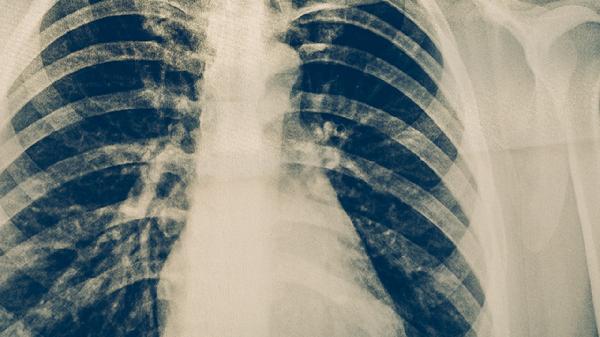

肺結(jié)核病的早期癥狀

肺結(jié)核病的早期癥狀主要有咳嗽、低熱、盜汗、乏力、食欲減退等。肺結(jié)核是由結(jié)核分枝桿菌感染引起的慢性傳染病,早期癥狀可能不明顯,容易被忽視。

肺結(jié)核早期最常見的癥狀是咳嗽,通常持續(xù)2周以上??人猿跗诳赡転楦煽龋S著病情發(fā)展可能出現(xiàn)咳痰,痰液可能呈現(xiàn)白色黏液狀或帶有血絲??人栽谠绯炕蛞归g可能加重,影響正常休息。肺結(jié)核引起的咳嗽與普通呼吸道感染不同,常規(guī)止咳藥物效果有限。若咳嗽持續(xù)不緩解,建議及時就醫(yī)進(jìn)行胸部影像學(xué)檢查和痰液結(jié)核菌檢測。

肺結(jié)核早期癥狀缺乏特異性,容易與其他呼吸道疾病混淆。若出現(xiàn)上述癥狀持續(xù)2周以上,建議及時到呼吸內(nèi)科或感染科就診。確診肺結(jié)核后應(yīng)嚴(yán)格遵醫(yī)囑進(jìn)行規(guī)范抗結(jié)核治療,常用藥物包括異煙肼片、利福平膠囊、吡嗪酰胺片、乙胺丁醇片和鏈霉素注射液等。治療期間應(yīng)注意休息,保持室內(nèi)通風(fēng),避免傳染他人。飲食上應(yīng)保證充足熱量和優(yōu)質(zhì)蛋白攝入,適當(dāng)補(bǔ)充維生素和礦物質(zhì)。定期復(fù)查胸部影像學(xué)和肝功能,監(jiān)測治療效果和藥物不良反應(yīng)。完成全程治療是治愈結(jié)核病的關(guān)鍵,不可擅自停藥或減量。